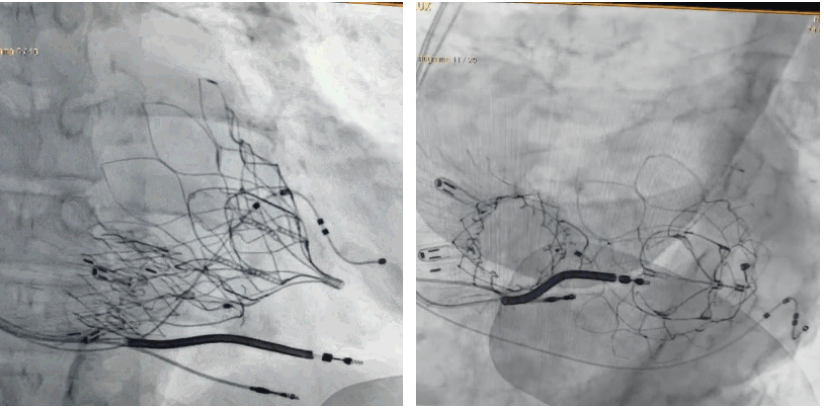

手術(shù)在全麻狀態(tài)下進行。術(shù)者采用經(jīng)右側(cè)頸靜脈入路的方式將輸送器送入患者心臟內(nèi),在TEE及DSA引導(dǎo)下調(diào)整輸送器頭端角度,使得輸送器與三尖瓣瓣環(huán)平面垂直。在輸送器進入右心室后釋放室間隔錨定裝置,而后釋放瓣葉夾持件(2個耳片結(jié)構(gòu))成垂直狀態(tài)。在TEE及DSA確定夾持件固定至三尖瓣葉根部且位于右室側(cè)后釋放人工瓣心房側(cè)盤片。隨后調(diào)整瓣膜同軸性以及室間隔錨定件位置(貼合室間隔),前推藏針管并固定,進而釋放室間隔錨定裝置,并再次確認瓣膜位置、穩(wěn)定性及同軸性,合攏輸送鞘后撤出輸送器,完成LuX-Valve Plus人工三尖瓣瓣膜的植入,僅殘余微量瓣周漏。且經(jīng)手術(shù)中心電生理團隊評估,病人的起搏器和ICD功能沒有受到影響。

術(shù)后DSA顯示Lux-Valve Plus與Tendyne和ICD無相互影響